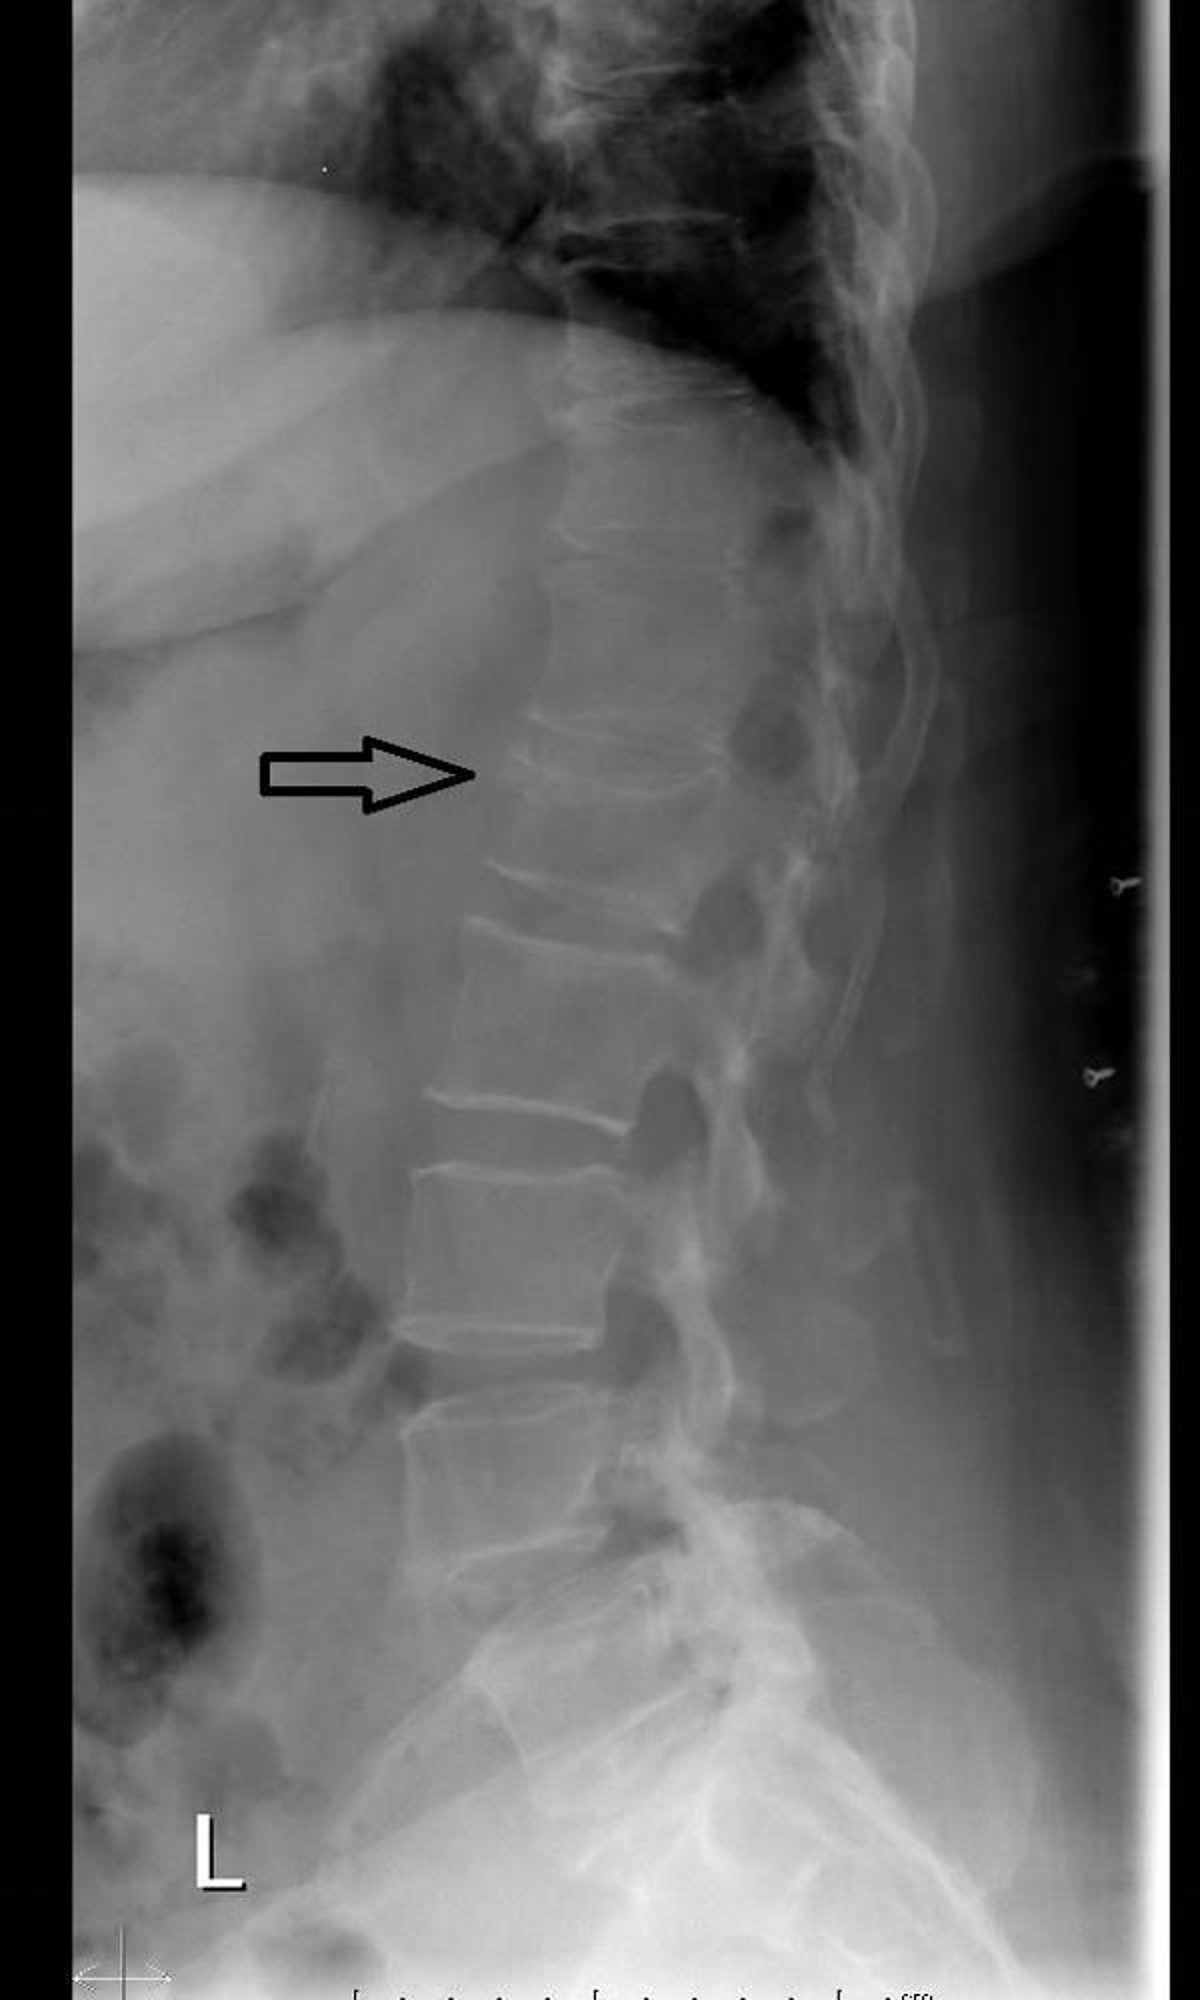

Компресійний перелом хребта (рентгенограма)

На рентгенограмі хребта у бічній проекції виявляється зменшення висоти та клиноподібна деформація хребця допереду внаслідок компресійного перелому.

Знімок люб'язно надано лікарем Даніелем Кампаньє [Danielle Campagne], MD.